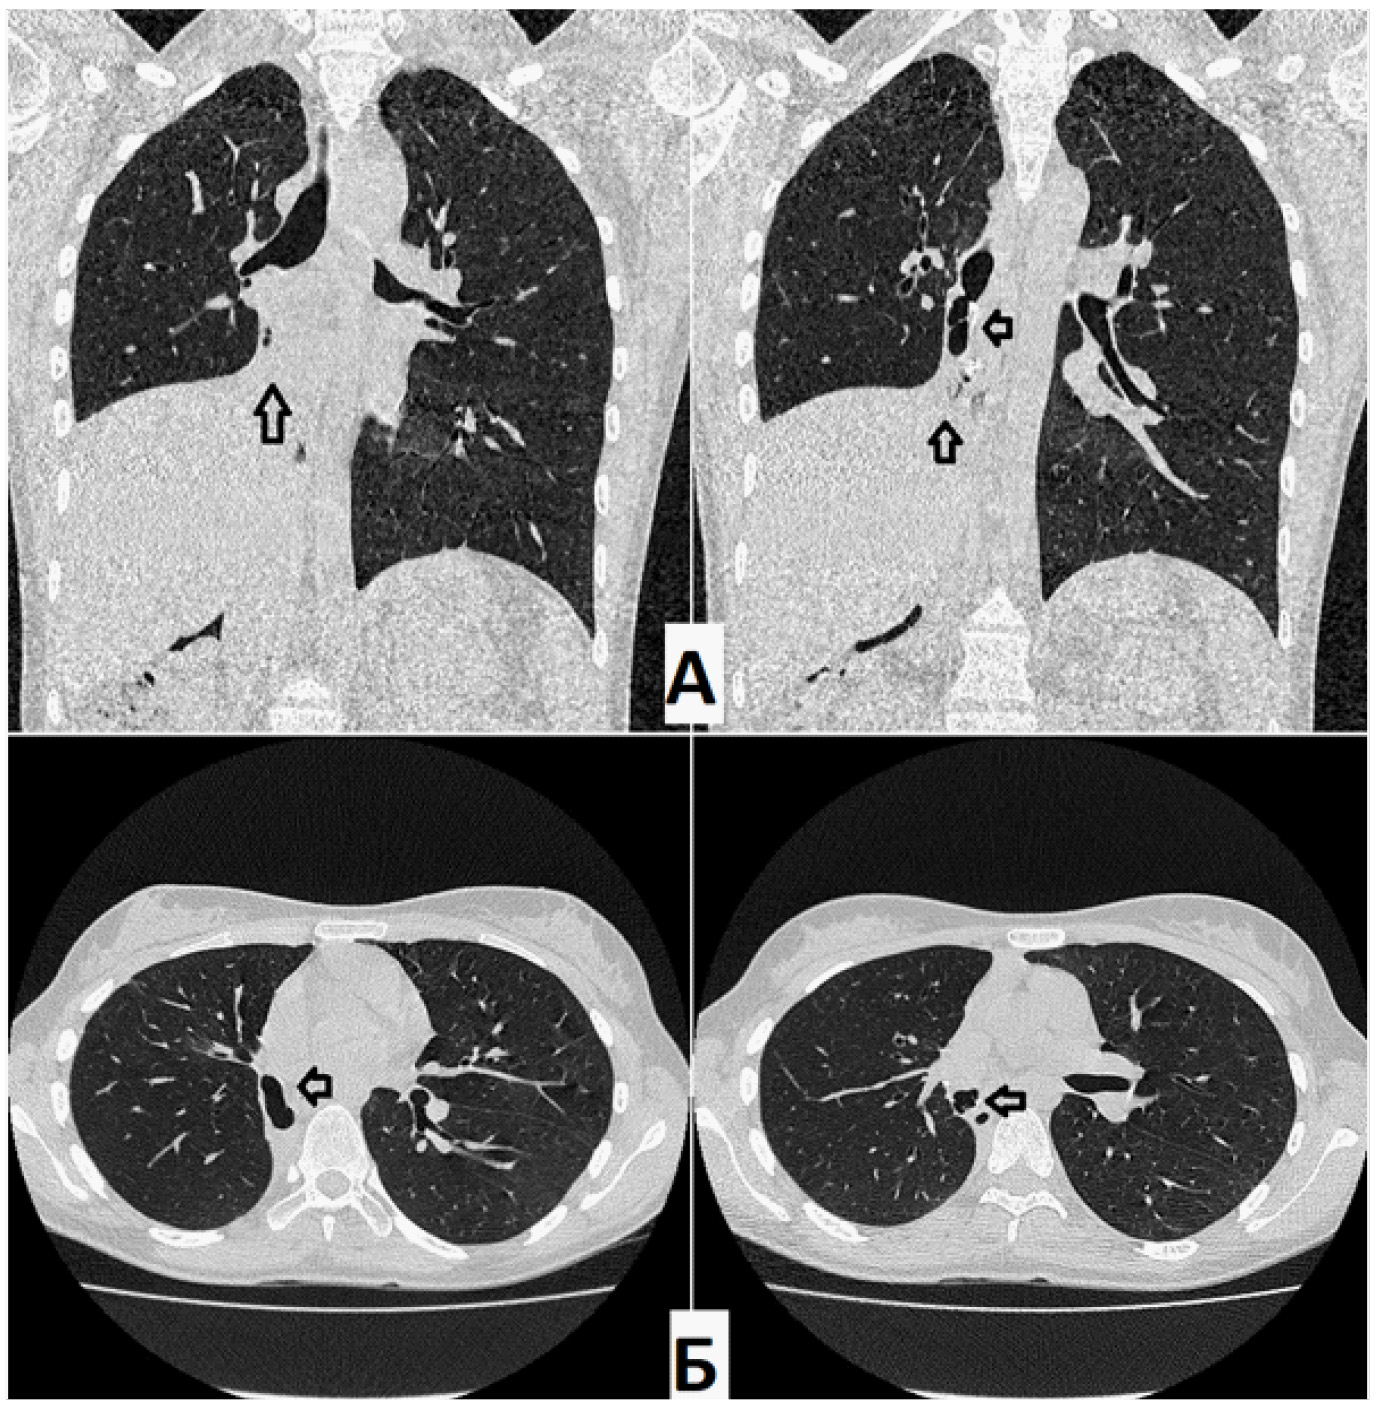

На КТ органов грудной клетки (от 21 июня 2021 г.) определялось бронхоплевральное сообщение культи правого промежуточного бронха с плевральной полостью. Остаточная плевральная полость (ОПП) в нижних отделах справа. В оставшихся отделах правого легкого – без патологических изменений (очаговых и инфильтративных теней не обнаружено). Тень средостения располагается срединно, правый купол диафрагмы приподнят до уровня VI межреберья (рис. 1).

Рис. 1. Компьютерная томография (А – фронтальная проекция; Б – аксиальная проекция) при поступлении. Определяется остаточная полость парамедиастинально слева